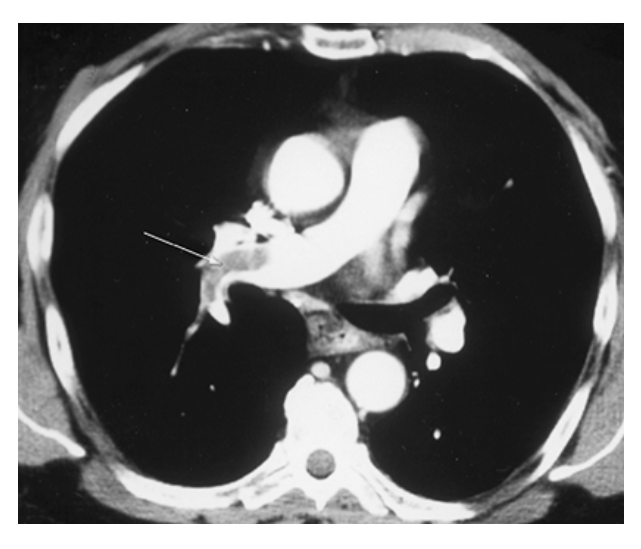

Pulmonary Emboli. CTPA shows large filling defect (clot) in the right main pulmonary artery (arrow) extending into the lower lobe pulmonary arteries.

Pulmonary Emboli. CTPA shows linear filling defect representing a clot in the left upper lobe pulmonary artery (arrow).